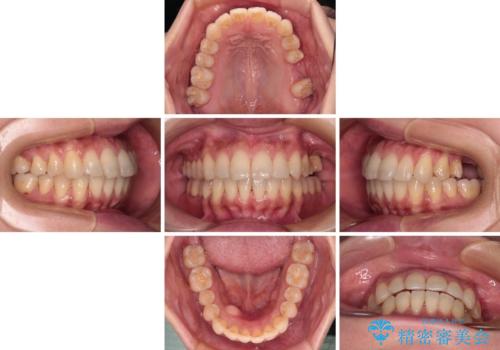

- 全体的なデコボコと、以前抜歯した歯のスペースを閉じた部分が気になるとのことで来院された患者様です。

左上第一大臼歯を抜歯した際に、スペースを閉じたそうですが、歯が傾斜してものが挟まって不快とのことでした。

インビザライン矯正で全体の歯列と整えるとともに、左上第一大臼歯部にはスペースを作り、インプラントによる補綴治療を行うこととしました。